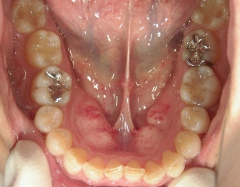

矯正歯科 治療前

矯正歯科(全顎ワイヤー矯正)治療後

全顎ワイヤー矯正 症例(2)

36歳女性 磐田市

在住

治療期間2年6

ヶ月